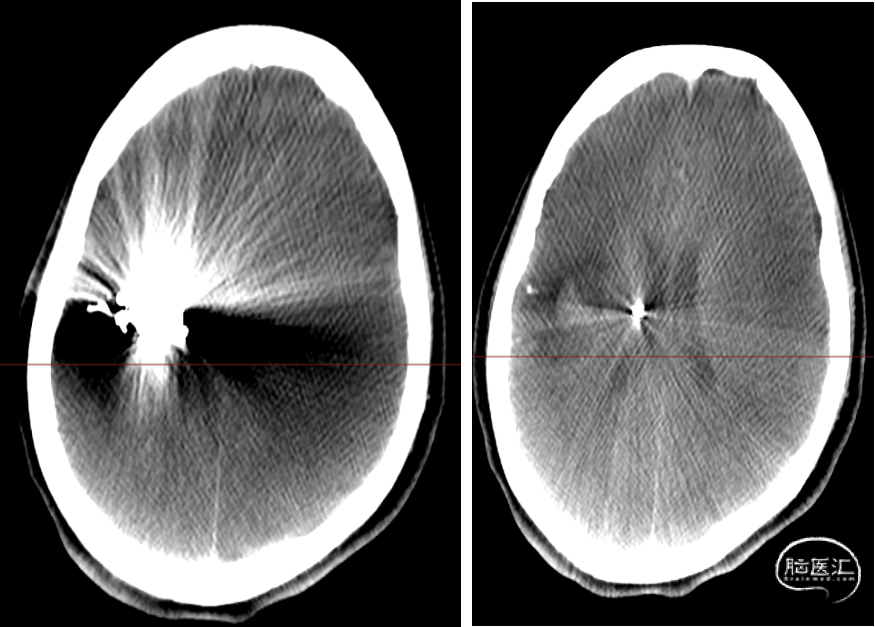

患者诉20余天前因“突发左上肢无力”,至当地医院就诊,行头颅CT检查后拟“脑出血”住院治疗,行脑血管造影检查发现“脑血管畸形”,经治疗,左上肢乏力逐渐好转;今为进一步治疗“脑血管畸形”来我院,门诊以“脑血管畸形”收入院。自发病以来,患者精神、食欲逐步恢复,进食可,大小便正常,体重无明显改变。

CBCT:无出血,术后无明显不适